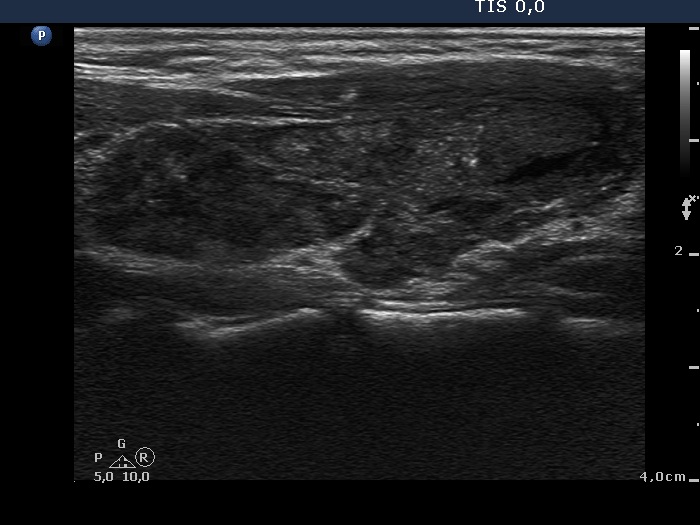

Examination 2 years later (3rd row of images)

Summary of follow-up: the size of the nodule became significantly lower at 6-week follow-up and was unchanged in the course of follow-up investigations. The patient had no complaints.

Functional state: euthyroidism on daily 100 microgram levo-tiroxine with TSH-level 0.96 mIU/L.

Ultrasonography: the basic ultrasound pattern of the thyroid was unchanged. An echonormal lesion was found corresponding to the former cystic nodule. The pretreatment volume decreased from 11.9 mL to 0.28 mL.

Suggestion: to continue the follow-up with ultrasound and TSH determinations every year.